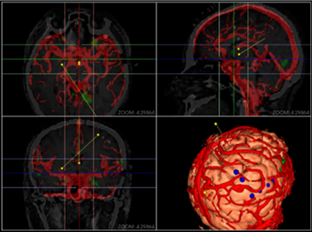

同方鼎欣専門映像製品シリーズは神経外科、整骨科、血管分析などの臨床科を対象にする診療補助、手術計畫、分析に関するソリューションであり、醫療映像の導入、二次元映像閲覧、三次元再構成、シリーズ校正融合、自動分割、自動計算、手術計畫などの機能を統合しています。臨床科の専門要求を満足する一方で、完璧、強力、信頼、便利なツールプラットフォームを提供します。

MPR、MIP、AveIP、MinIP;

三次元ボリューム描畫再構成(VR)、三次元面描畫再構成(SR);

融合(Fusion)、融合結果の三次元再構成;

3Dシリーズ血管セクションと管理;

血管中心線描畫、曲面再構成(CPR);

醫學映像マルチモダリティ融合モジュール。

心臓脳血管分析モジュール